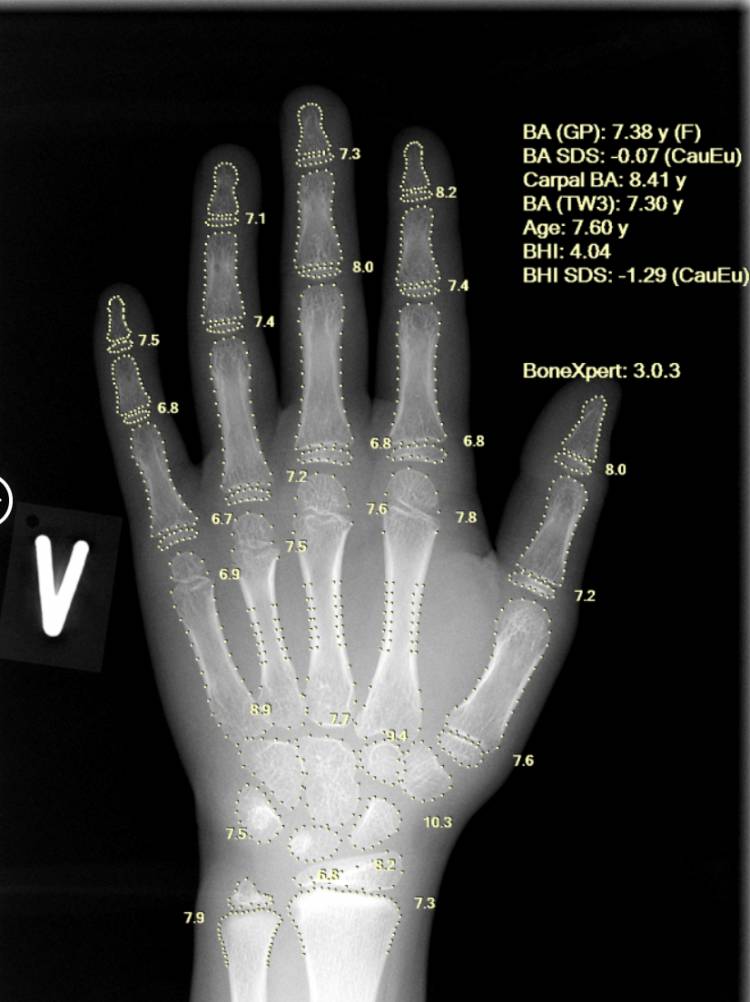

Using a single left-hand X-ray, BoneXpert provides a comprehensive, multi-method assessment, including Greulich-Pyle (GP) bone age, Tanner-Whitehouse (TW2/TW3) bone age, carpal bone age, as well as Bone Age SDS and Bone Health Index (BHI). This depth of analysis enhances diagnostic confidence and supports clinicians in early identification of constitutional growth delay and endocrine abnormalities at an early stage.